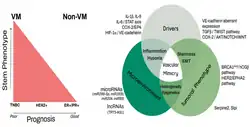

Epithelial-mesenchymal transition (EMT)

EMT is thought to be one of the major drivers of VM in cancer.[10] This is a mechanism through which cancer cells lose their epithelial properties resulting in a loss of cell-cell adhesion and a transition towards mesenchymal-like properties . EMT plays a diverse and essential role in adhesion, motility and morphology of cells under both normal and pathological conditions. When cells undergo EMT, they lose their polarity, ability to adhere to neighboring cells, and the tight contacts as result of losing expression of epithelial cell markers such as E-cadherin. Cells that have taken on mesenchymal properties are non-adherent, and thus promote invasion into nearby tissues. This process occurs normally in wound healing as well as embryonic development.[11] This transition process has been identified to occur in cancer cells and drives metastasis and invasion into other tissues.[11] EMT is associated with increasing and maintaining the VM in tumors through several pathways such as Twist transcription factor, and TGFB.[12][13] Importantly to VM, the process of EMT results in the loss of E-cadherin, and the promotion of VE-cadherin transcription and expression, a critical factor in development of vascular mimicry.[3] EMT is also implicated in promotion of stem-like properties in cancer cells.[14]

Cancer stem cell signaling (CSCs)

Cancer stem cells (CSCs) is a theory which explains the heterogeneity of tumors. This theory states that tumors arise from a small subpopulation of cancer cells which have the ability to self-renew as well as differentiate.[15] These CSCs give rise to unique cell subpopulations within the tumor through differentiation, which express unique cell characteristics that further drive tumor growth and metastasis. CSCs have been linked to driving VM formation predominantly through the secretion of VEGF, which is a well established regulator of VE-cadherin expression.[10] Within the CSCs, several studies have identified specific subtypes of cancer stem cells which are linked to promoting VM formation, including stem cells expressing CD133+ in acute leukemia,[10] melanoma,[10] and Triple negative breast cancer (TNBC).[3]

Breast cancer

New strategies to overcome treatment resistance in breast cancers have looked to target tumor angiogenesis and the problem posed by vascular mimicry in treatment resistance.[18] The presence of VM in breast cancer has been associated with the more challenging to treat triple negative breast cancer (TNBC). In addition, VM has been found to be more predominant in HER2 positive breast cancer, increase the presence of Epithelial-mesenchymal transition markers, and increased stem-like properties of breast cancer cells.[18] In a study of malignant breast cancers, 35% of reported cases of TNBC were found to be VM+, while only 17.8% of non-TNBC were found to be VM+.[9]

Melanoma

Melanoma is an aggressive skin cancer which has been shown to utilize both angiogenesis and vascular mimicry to drive metastasis and also increase treatment resistance.[1] Metastatic melanoma has very poor survival outcomes with a median survival of 6 months.[19] VM has been identified to be present only in metastatic and very aggressive melanomas. Major biomarkers of VM in melanoma include: VEGF-A, HIF-1A, and Nodal.